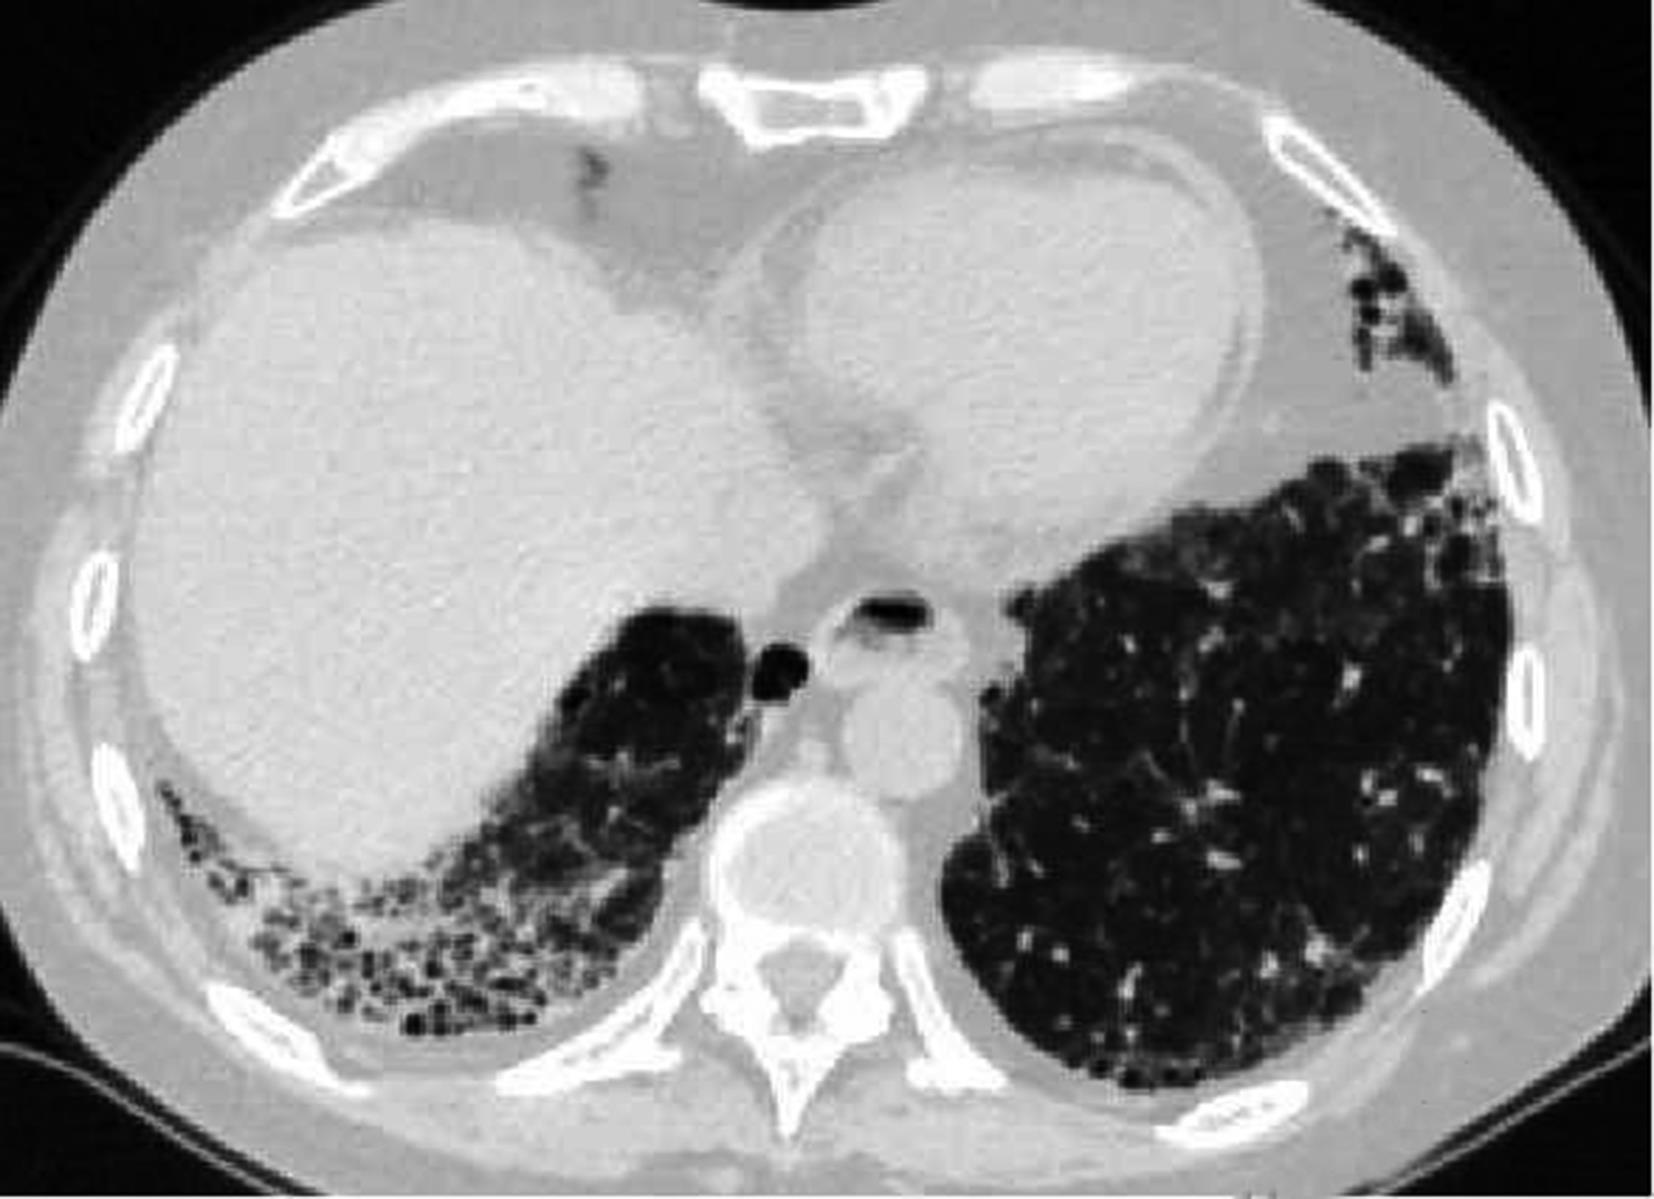

• 系统性红斑狼疮患者肺部影像学特征与疾病活动度相关性研究

2023, 48(11):1351-1355. DOI: 10.13406/j.cnki.cyxb.003353

摘要 (94) HTML (39) PDF 1.35 M (174) 评论 (0) 收藏

摘要:目的 探讨系统性红斑狼疮合并间质性肺病的CT特征与疾病活动度的相关性。方法 纳入131例系统性红斑狼疮相关间质性肺病患者。分析其疾病活动度评分、影像学特征及高分辨CT(high resolution computed tomography,HRCT)肺间质纤维化Kazerooni评分。采用Spearman秩和相关系数检验分析各评分之间的相关性。结果 Kazerooni评分法中的磨玻璃评分与系统性红斑狼疮疾病活动度-2000评分(systemic lupus erythematosus disease activity index-2000,SLEDAI-2000)呈正相关,差异有统计学意义(rs=0.388,P<0.001)。而纤维化评分与SLEDAI-2000评分之间差异无统计学意义(P=0.837)。弥漫性肺泡损伤(diffuse alveolar damage,DAD)组磨玻璃评分得分最高,寻常型间质性肺炎(usual interstitial pneumonia,UIP)组纤维化评分得分最高,差异有统计学意义(均P<0.001)。比较不同间质性肺病(interstitial lung disease,ILD)类型之间SLEDAI-2000评分差异无统计学意义(P>0.05)。结论 胸部HRCT可有助于更全面地评估系统性红斑狼疮疾病情况,对制定治疗方案具有重要意义。